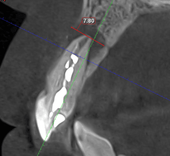

We decided to perform microsurgery. Through a small, precise access point, we carefully removed the воспалatory lesion at the root tip, cleaned the affected tissues, and sealed the area securely. The goal was to eliminate the source of infection while preserving the natural tooth.

Six months later, the fistula resolved and the bone regenerated. The tooth was saved and is functioning normally.